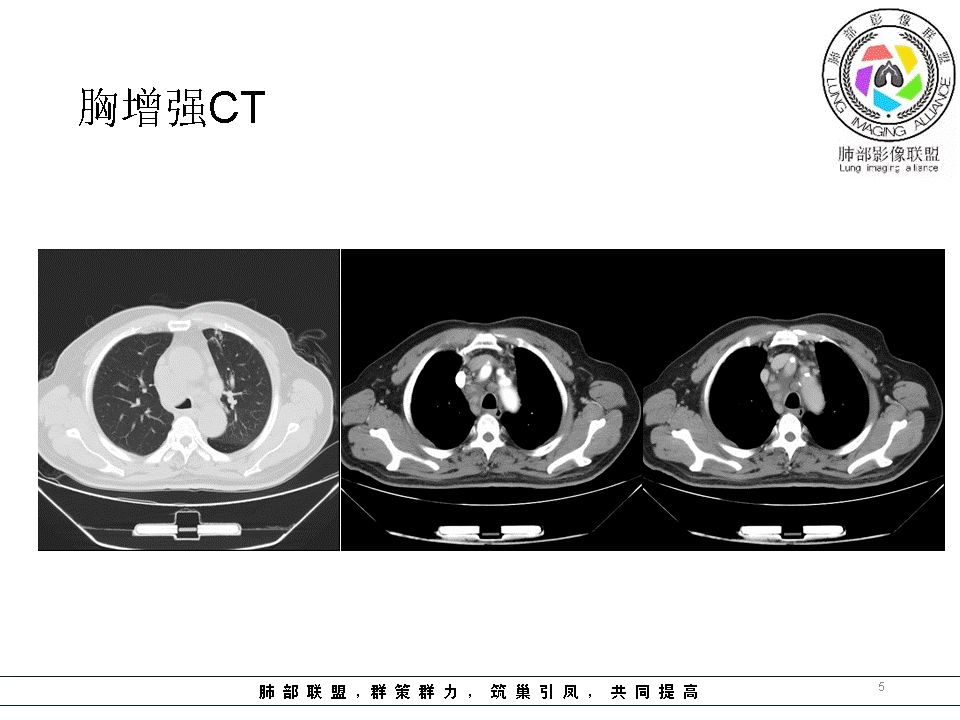

南边:临床:老年男性,病史偏长,2月。临床有通气功能障碍。

我们看影像,肺内有一些小斑点状高密度影,部分区域有气体潴留:

南边:但是我们看纵隔就多发的肿大淋巴结,部分融合成团。

南边:而且这些淋巴结,有些直接主要是压迫支气管壁,但是有些是突入到支气管腔内的。可惜我截的图发不上来。就左上舌段,支气管壁明显的增厚。有些明显腔内突的一个结节的,但是远的没有阻塞的特点。南边:增强以后呢,这个病灶明显强化,部分的似乎有环形强化的迹象,但不是很典型。

我们看这个主支气管的层面,主支气管明显受压,有变形的,但是软骨是没有突破的。

结果:肺腺癌并纵膈淋巴结转移